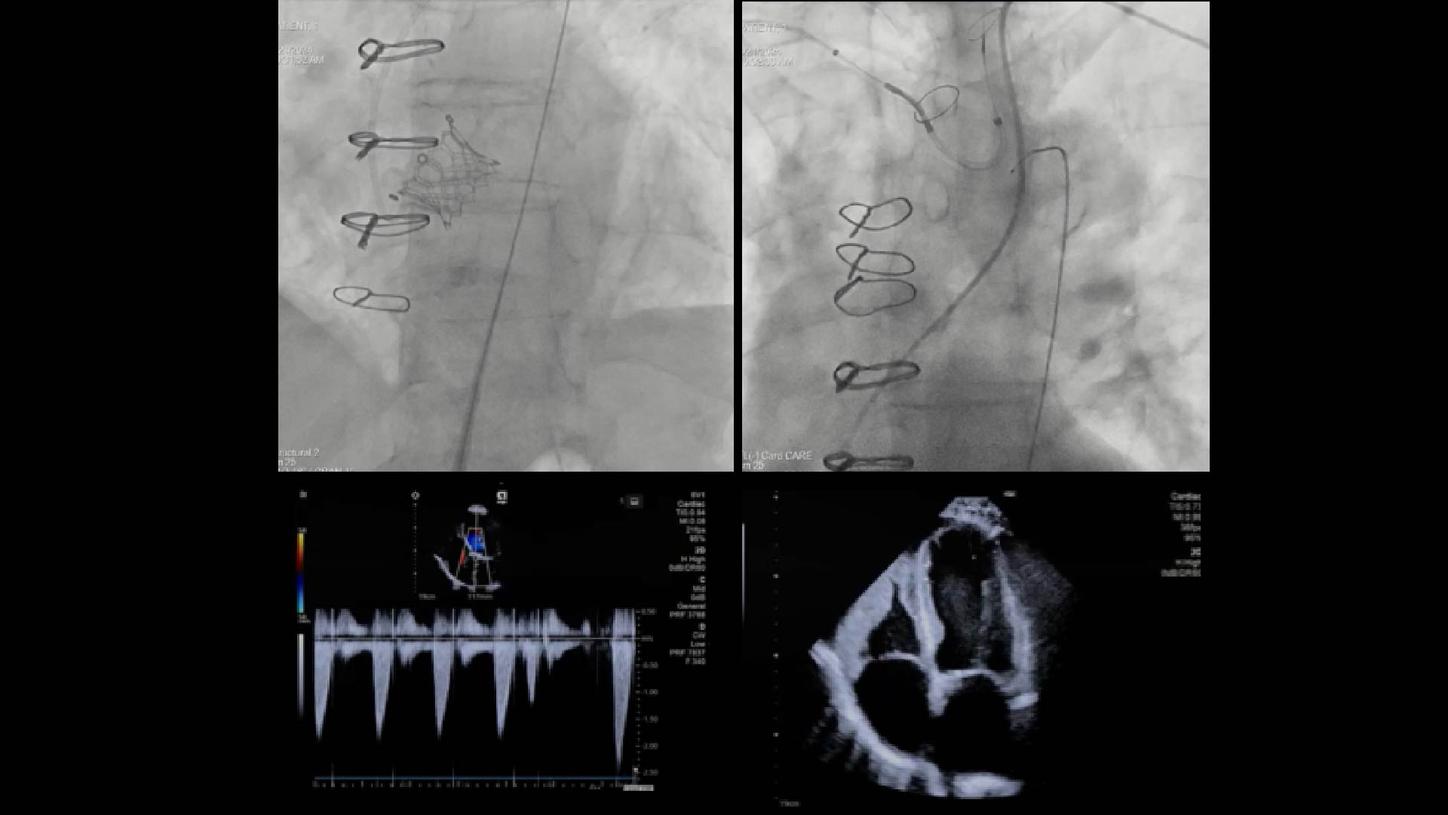

- Colocación y despliegue del dispositivo SENTINEL™

- Colocación del guía y del dispositivo con syngo Aortic Valve Guidance

- Despliegue del dispositivo SAPIEN 3

Objetivo clínico: Soporte para la colocación de un dispositivo de protección cerebral como herramienta para mitigar el riesgo de accidente cerebrovascular embólico.

Soluciones y características seleccionadas: ARTIS pheno, Case Flows, Una combinación preestablecida de configuraciones (angulación, disposición de la pantalla, etc.), personalizada para la colocación del dispositivo SENTINEL™*, reduce las interacciones con el sistema. Con Case Flows, una única interacción del usuario reemplaza el ajuste de hasta 6 configuraciones del sistema³. syngo 2D/3D Fusion - Aplicación para superponer la anatomía de la arco aórtico basada en tomografía computarizada sobre fluoroscopia en vivo, para apoyar la navegación del dispositivo. Se ha demostrado que la guía por fusión reduce significativamente el tiempo de despliegue del dispositivo SENTINEL™* y el uso de contraste⁴.

Soluciones y características seleccionadas: 3mensio (Pie Medical Imaging) Software semiautomatizado para asistir en la reconstrucción 3D de la válvula previamente implantada y la anatomía circundante, con el fin de determinar el abordaje ideal y el tamaño adecuado de la válvula. Su uso reduce el tiempo de planificación del TAVR¹ y los resultados de la planificación pueden exportarse para superposición en tiempo real durante la fluoroscopia.